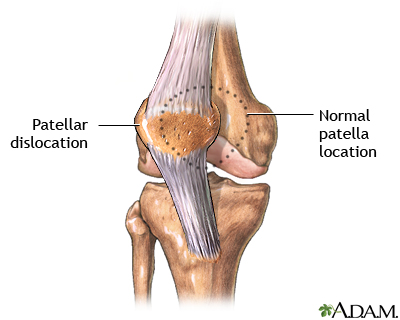

Kneecap dislocation occurs when the round-shaped bone covering the knee (patella) moves or slides out of place. The dislocation often occurs toward the outside of the leg.

Dislocation may also occur as result of direct trauma. When the kneecap is dislocated, it can slip sideways to the outside of the knee.